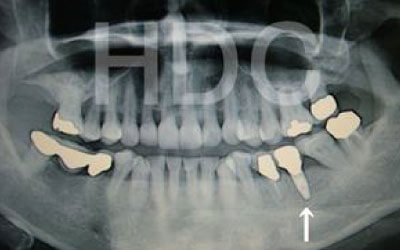

骨が薄い場合、そのままインプラントを行うのはお勧めできません。

ただし、事前に骨を増やす治療を行ったり、インプラントと同時に骨を増やす治療を行えば、インプラントは可能です。